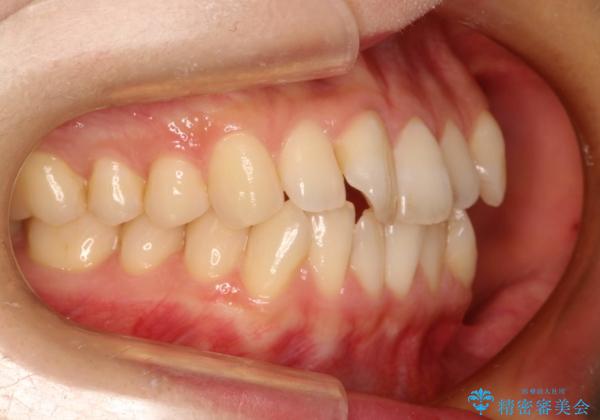

前歯のガタガタをインビザラインで目立たず矯正

- 目立たずに前歯を矯正したいとのことで来院されました。

歯と歯の間にわずかに隙間を作りスペースを確保し、インビザラインにて矯正を行うこととなりました。

前歯の微調整に少し時間がかかりましたが、整った歯並びにすることができました。